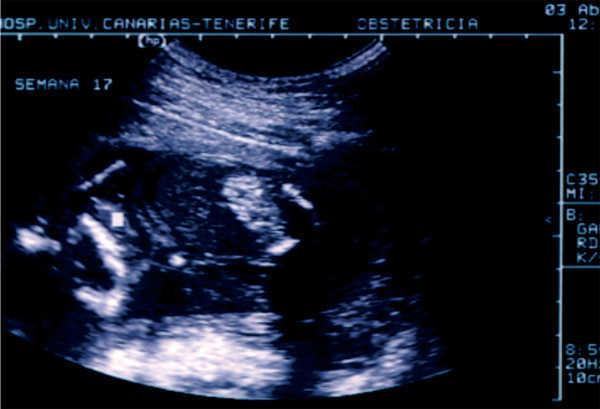

Hemos tenido la oportunidad de estudiar un niño que, actualmente, tiene 3 años de edad. Fue remitido por su pediatra a los 5 meses de vida tras un episodio de hematuria macroscópica, en el que se objetivó la presencia de un cálculo en el pañal. Se trata del primer hijo de unos padres no consanguíneos, sin patología previa de interés y con antecedentes de miembros con cólicos nefríticos en la rama paterna. Durante la gestación se detectaron en los controles ecográficos fetales una hiperecogenicidad del colon en ausencia de otras anomalías intestinales (figura 1 y figura 2) y una luminiscencia nucal discretamente aumentada, sin otros hallazgos de interés. Por este motivo, al nacimiento se realizó un test del sudor para descartar la presencia de fibrosis quística, cuyo resultado fue normal.

Describimos de esta forma un caso de cistinuria de presentación clínica temprana, reflejo de la gran capacidad litogénica que posee esta entidad, con la particularidad del hallazgo ecográfico prenatal de hiperecogenicidad del colon secundaria al depósito de cristales de cistina en dicha localización. Esta forma de presentación de la cistinuria fue descrita en 20063 y confirmada posteriormente4. La explicación de este hallazgo radica en que los cristales de cistina se forman intraútero en el riñón fetal, pasan al líquido amniótico y, posteriormente, son deglutidos. El hallazgo ecográfico de la hiperecogenicidad intestinal intraútero ha sido relacionado clásicamente con la fibrosis quística, motivo por el que se realizaron los estudios necesarios para descartar esta enfermedad al nacimiento de nuestro paciente. Su negatividad y la clínica tan precoz permitieron el diagnóstico. El conocimiento de esta asociación puede conducir al diagnóstico precoz de la enfermedad, lo que permitirá establecer un tratamiento adecuado.

Figura 2. La misma situación al comienzo del segundo trimestre de gestación.